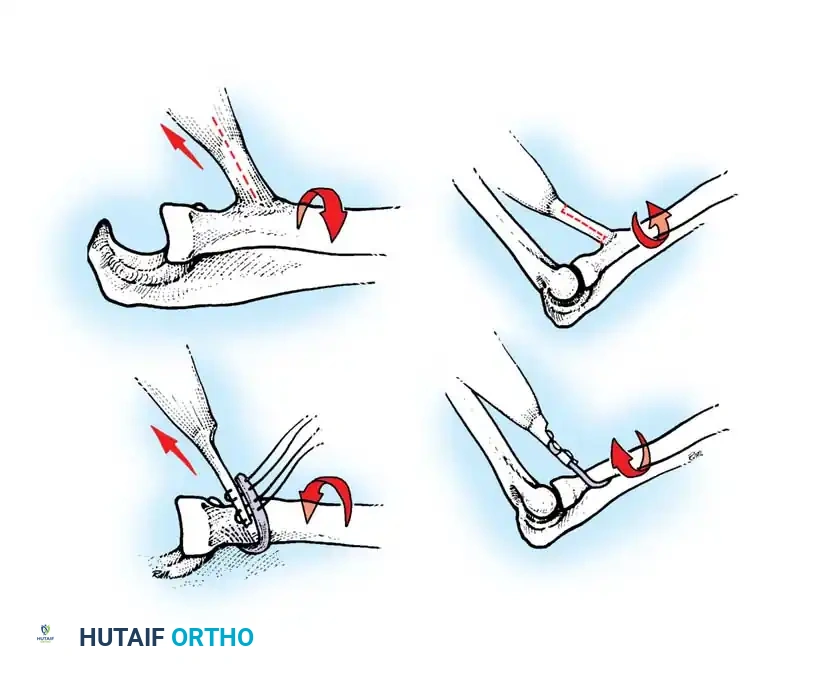

Setting the Tension (The Critical Step):

1. The tension of the transfer dictates the functional outcome. The goal is to provide maximum extension power without permanently eliminating passive elbow flexion.

2. Adduct the arm and fully extend the elbow. Place the deltoid under maximal physiological tension.

3. Preliminarily suture the graft to the triceps aponeurosis or directly into an olecranon bone tunnel.

4. Test the passive range of motion. You must be able to passively flex the elbow to at least 90 degrees (some authors advocate for full passive flexion, though this risks a lax transfer). If the transfer is too tight, the patient will lose the ability to bring the hand to the mouth.

5. Once optimal tension is confirmed, permanently secure the graft. Place stainless steel surgical markers (clips) at measured distances proximal and distal to the repair site. This allows for radiographic verification of repair integrity postoperatively (Ejeskär technique).

1. Immobilization: The arm is immobilized in a long-arm cast or rigid orthosis with the elbow at 30 degrees of flexion for exactly 4 weeks. Immobilizing in full extension risks severe joint stiffness, while excessive flexion risks stretching the transfer.

2. Early Mobilization (Weeks 4-8): The cast is removed, and a hinged elbow brace is applied. Active range-of-motion exercises within a protected arc are initiated. Gravity-eliminated exercises are utilized first. Passive stretching of the triceps is strictly prohibited.